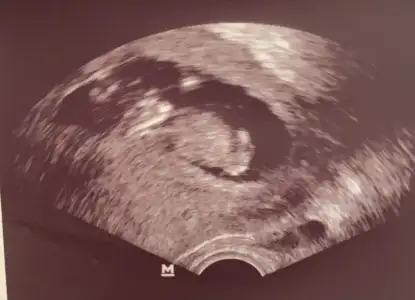

Sanki sanki kız gibi emin olamadım başka USG varsa paylaşın11+6dayım vajinaltahmininiz nedir

Anketimide oylarsaniz10haftalık ultrasonu atmıstım bide orda kız gibi demiştin ama yanıltıcı olabilir demiştin biri saklıyor biraz da ondan yanılttı bizi

![]()